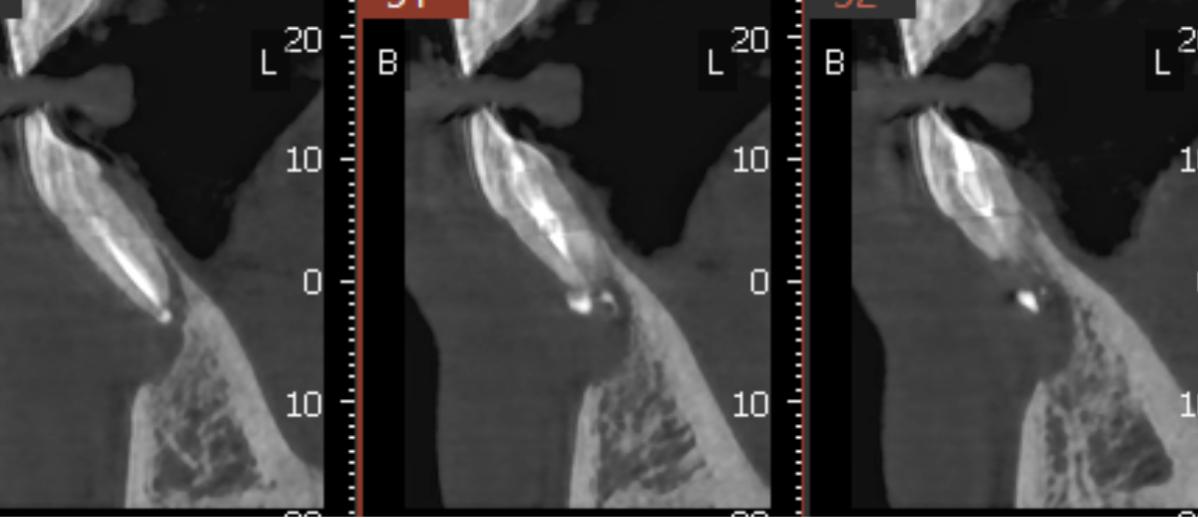

Se le realiza un TAC donde se observa una imagen radio lúcida de 11,3 mm de ancho y 8,5 mm de largo Esta imagen es compatible con un quiste odontogenico del 41 posiblemente causado por un fracaso endodontico. La imagen radiográfica afecta también al 42 pero dicho diente está vital. Se realiza un colgajo para hacer la quistectomía y apiceptomía del 41. Se regenera con hueso autólogo: xenoinjerto en una proporción 70:30 y membrana de colágeno STD de media reabsorción.